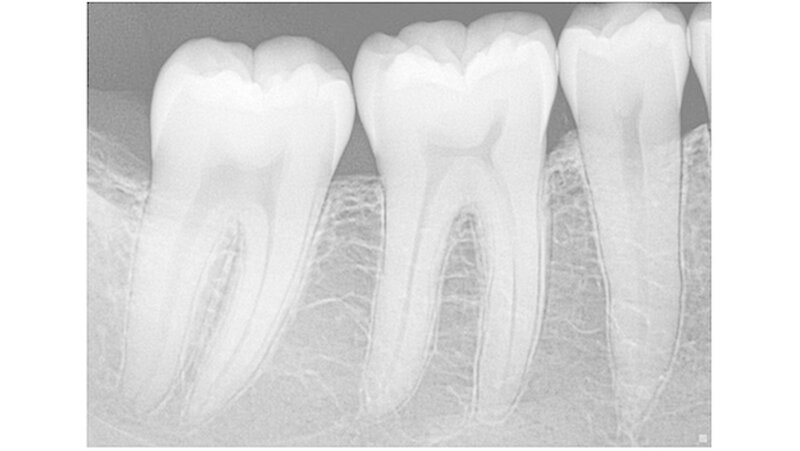

Röntgengeräte sind, wie die Behandlungseinheit, feste Bestandteile fast einer jeden Zahnarztpraxis. Analoge Systeme werden immer seltener weiter betrieben. Ein digitales intraorales Röntgensystem ist zum Beispiel für die Kariesdiagnostik von Vorteil (und hier insbesondere im approximalen Bereich), für die Endodontie, für parodontale Fragestellungen. Ein Panoramaröntgengerät mit digitalem Sensor für OPG-Aufnahmen bietet zusätzlichen Nutzen.

Mit 22 Linienpaaren pro Millimeter beziehungsweise der Darstellung von Details bis auf 12,5 Mikrometer (entsprechend einem ISO-06-Endo-Instrument) werden in der Praxis feinste Strukturen präzise abgebildet. Der Anteil der Speicherfolientechnik lässt sich nur grob schätzen und dürfte zurzeit etwa in Größenordnungen von 60 Prozent gegenüber 40 Prozent (oder 50 zu 50) für Sensoren liegen.

Der Sensor spielt seine Vorteile dort aus, wo es um Schnelligkeit geht, bei der Endo-Kontrollaufnahme oder bei Serienaufnahmen für die Kariesdiagnostik. Auch scheinen in der Sensortechnologie noch Fortschritte möglich, die zu einer Verbesserung der Bildqualität führen könnten. Zum einen lassen sich, parallel zur allgemeinen Entwicklung in der Elektronik, immer mehr Informationen auf einem Chip speichern.